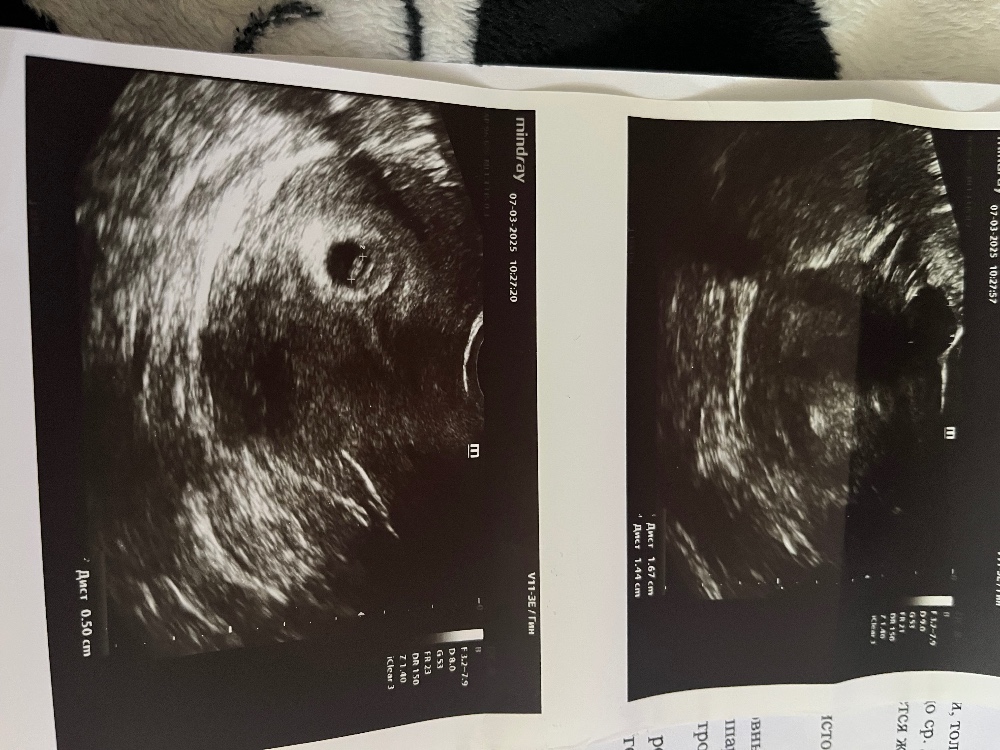

в пятницу ктр был 5, плодное яйцо 9,7. Я начиталась таких ужасов за это время. У 95% всех ситуаций была в итоге замершая при таких показателях. Я уже настроила себя на самое плохое.

Криво намеряли,пя если плохо растет,то оно и потом плохо растет,а у вас нормально росло,врятли за 5 дней оно так выросло,у вас сейчас получается свд пя 21,оно растет примерно 1 мм в сутки,значит 5 дней назад было не 9,7,а 16 мм,а у вас точно пя свд 9,7 было или там несколько размеров,как здесь,просто смотрят не какую-то одну сторону,а считают свд,если три значения,то их складывают и делят на 3,если два,то анологично складывают и делят на 2 уже

Марина, да, в прошлый раз сказали свд-9,7 мм. Мерили по 2м сторонам. Каждая из сторон была 9 с чем-то. В общем, не понимаю как так могли намерить.